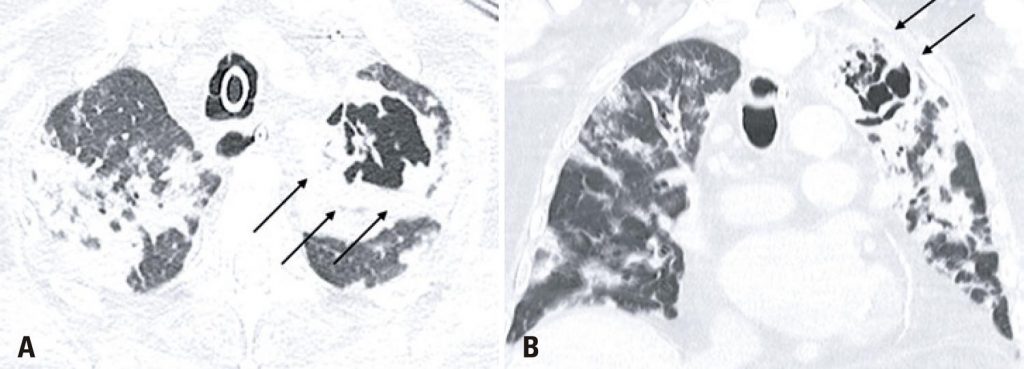

Paciente do sexo masculino com 86 anos de idade, foi admitido no nosso serviço de emergência com história de 1 dia de febre, dispneia e tosse. Após avaliação, não houve critérios que justificassem sua internação, sendo liberado com orientações e tratamento domiciliar. Uma semana após o aparecimento dos sintomas, o paciente retornou ao serviço demostrando piora da dispneia e persistência da febre, o que motivou sua internação. A tomografia computadoriza (TC) do tórax demonstrou achados típicos de infecção pelo coronavírus (COVID-19)(,) (), e o resultado do teste de reação em cadeia da polimerase (PCR) em tempo real confirmou o diagnóstico. No décimo terceiro dia de hospitalização, o paciente apresentou degeneração clínica, sendo diagnosticado com pneumonia nosocomial causada por Enterococcus faecalis (). Nova TC 10 dias após o diagnóstico da infecção hospitalar mostrou múltiplas opacidades em vidro fosco, juntamente de espessamento septal e áreas de consolidação, achados possivelmente ainda relacionados à COVID-19. Observou-se também uma lesão escavada no lobo superior esquerdo (), achado novo em relação à última tomografia. Novo teste de PCR demostrou infecção ainda positiva para COVID-19 no mesmo dia da última TC.